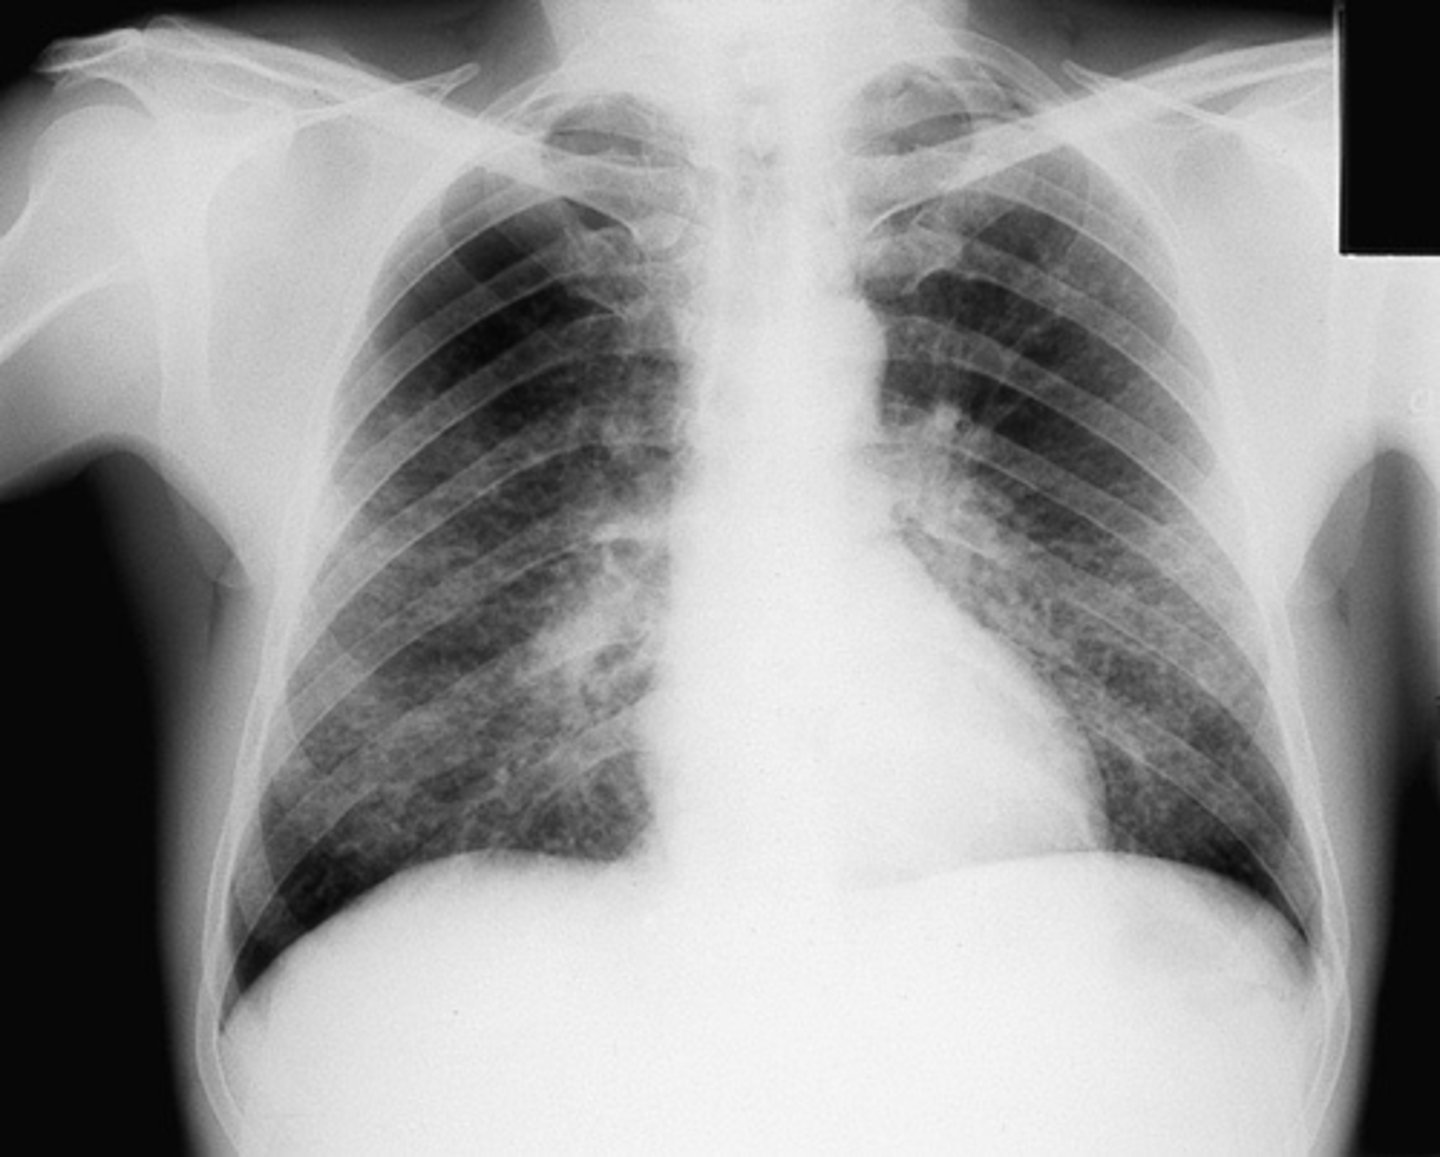

community acquired pneumonia

Silhouette sign

CAP- interstitial

CAP- round

Silhouette sign right cardiac border- RML infiltrate

Silhouette sign right cardiac border, RML